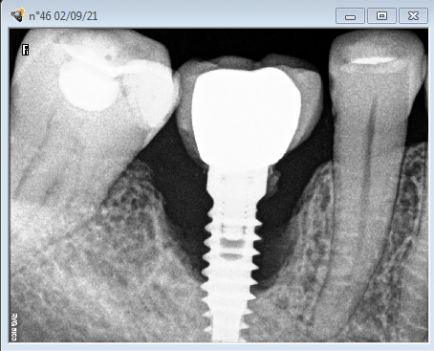

Este curso te ayuda a comprender porque la colocación de implantes dentales son altamente predictivos, la posibidad de fracaso y sus complicaciones clínicas. La observación detenida y el diagnóstico planificado de los tejidos duros y blandos a tratar le garantiza al paciente y al profesional el éxito del tratamiento.

Este curso ofrece las bases biológicas para entender el porqué de la mucositis y comprender por qué 1 paciente con implante de cada 4 desarrolla Periimplantitis.Incluye los factores de riesgo y como tratarlos de forma predictiva en el tiempo.